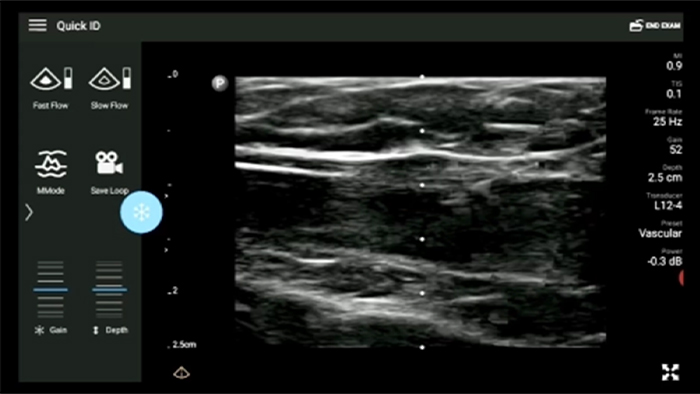

Disminuya las complicaciones de las inserciones de CVC

La guía por ultrasonido en tiempo real puede mejorar la precisión y la seguridad de las inserciones de CVC.

Transductor de matriz lineal de banda ancha Lumify L12-4

• Rango extendido de frecuencias de operación entre 12 y 4 MHz • Tamaño de apertura: 34 mm • 2D, Doppler orientable a color, Modalidad M, XRES avanzado e imágenes armónicas multivariables, SonoCT • Imágenes de alta resolución para aplicaciones superficiales: tejidos blandos, vasculares, superficiales, musculoesqueléticos y pulmonares • Marcador de línea central • Transductor USB-C con cable reemplazable